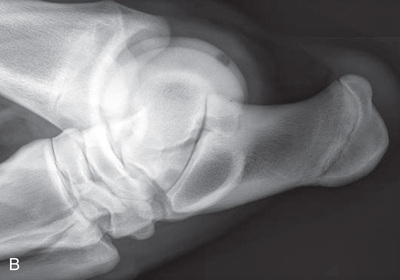

Digit/foot: P-III (distal phalanx, coffin bone) P-II (middle phalanx) P-I (proximal phalanx-pastern) Proximal interphalangeal joint (pastern joint) joint | DP (Standard) (Fig. 24.62B,C) | Dorsal 45-degree proximal–palmarodistal (D45Pr-PaDi) | Foot slightly forward on image receptor. | Perpendicular to foot axis at MSP (midsagittal plane) at area of interest with beam angled ~45 degrees to ground |

| Lateral (Standard) (Fig. 24.62D) | Lateromedial | On a block to elevate limb for P-III; resting on ground for other views. | 90 degrees lateral to MSP, parallel to ground on area of interest: coronary band for PIII | |